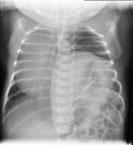

During the study period, there were 533 foetal deaths from GA 20 weeks, and 369 infants died before the age of one year in the study area. This gives a combined foetal and infant mortality of 11.6 per 1,000 births ranging from 13.5 in 1995-1999 to 10.2 in 2000-2004 (Figure 1). A total of 59 of the 533 foetal deaths (11.1%) had a major congenital anomaly, and 115 of 369 infant deaths (31.2%) had a major congenital anomaly. This gives a foetal and infant mortality with congenital anomalies in the population of 2.2 per 1,000 births with a significant decline from 1995-1999 to 2005-2008 (from 2.8 per 1,000 births to 1.5 per 1,000 births, p = 0.0055) (Figure 1). Mortality with congenital anomalies within the first week after birth declined from 1.14 per 1,000 births in 1995-1999 to 0.32 per 1,000 births in 2005-2008 (p = 0.0101). There was no change in total mortality within the first week after birth in these two periods (3.20 and 3.18 per 1,000 births, respectively), which means that 35% of all first-week deaths in 1995-1999 were associated with a major congenital anomaly, whereas only 10% of all first-week deaths in 2005-2008 were associated with a major congenital anomaly.